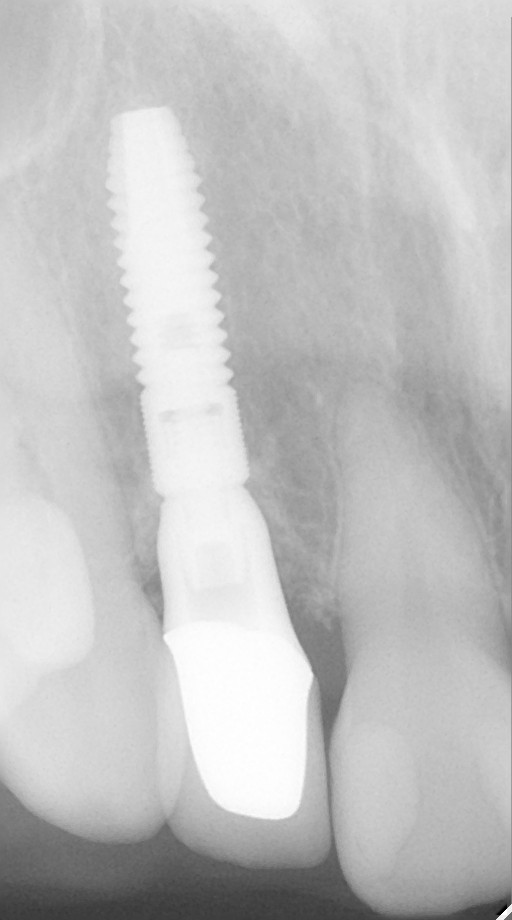

インプラント治療の症例紹介②

Before

After

主訴

前歯の脱落、歯肉の腫れ

治療内容

修復物の脱落時に支台築造のポスト部で歯質を破折。抜歯即時インプラント埋入をおこなったケース。

治療費

473,000 円(税込)

治療期間

8か月

治療回数

12回

想定されたリスク

※経年的な歯肉退縮の恐れ、インプラント周囲炎の恐れがありました。

残存した歯根に感染が少なく、抜歯時即時にインプラント埋入手術を行った。術後〇年経過し安定している状態。